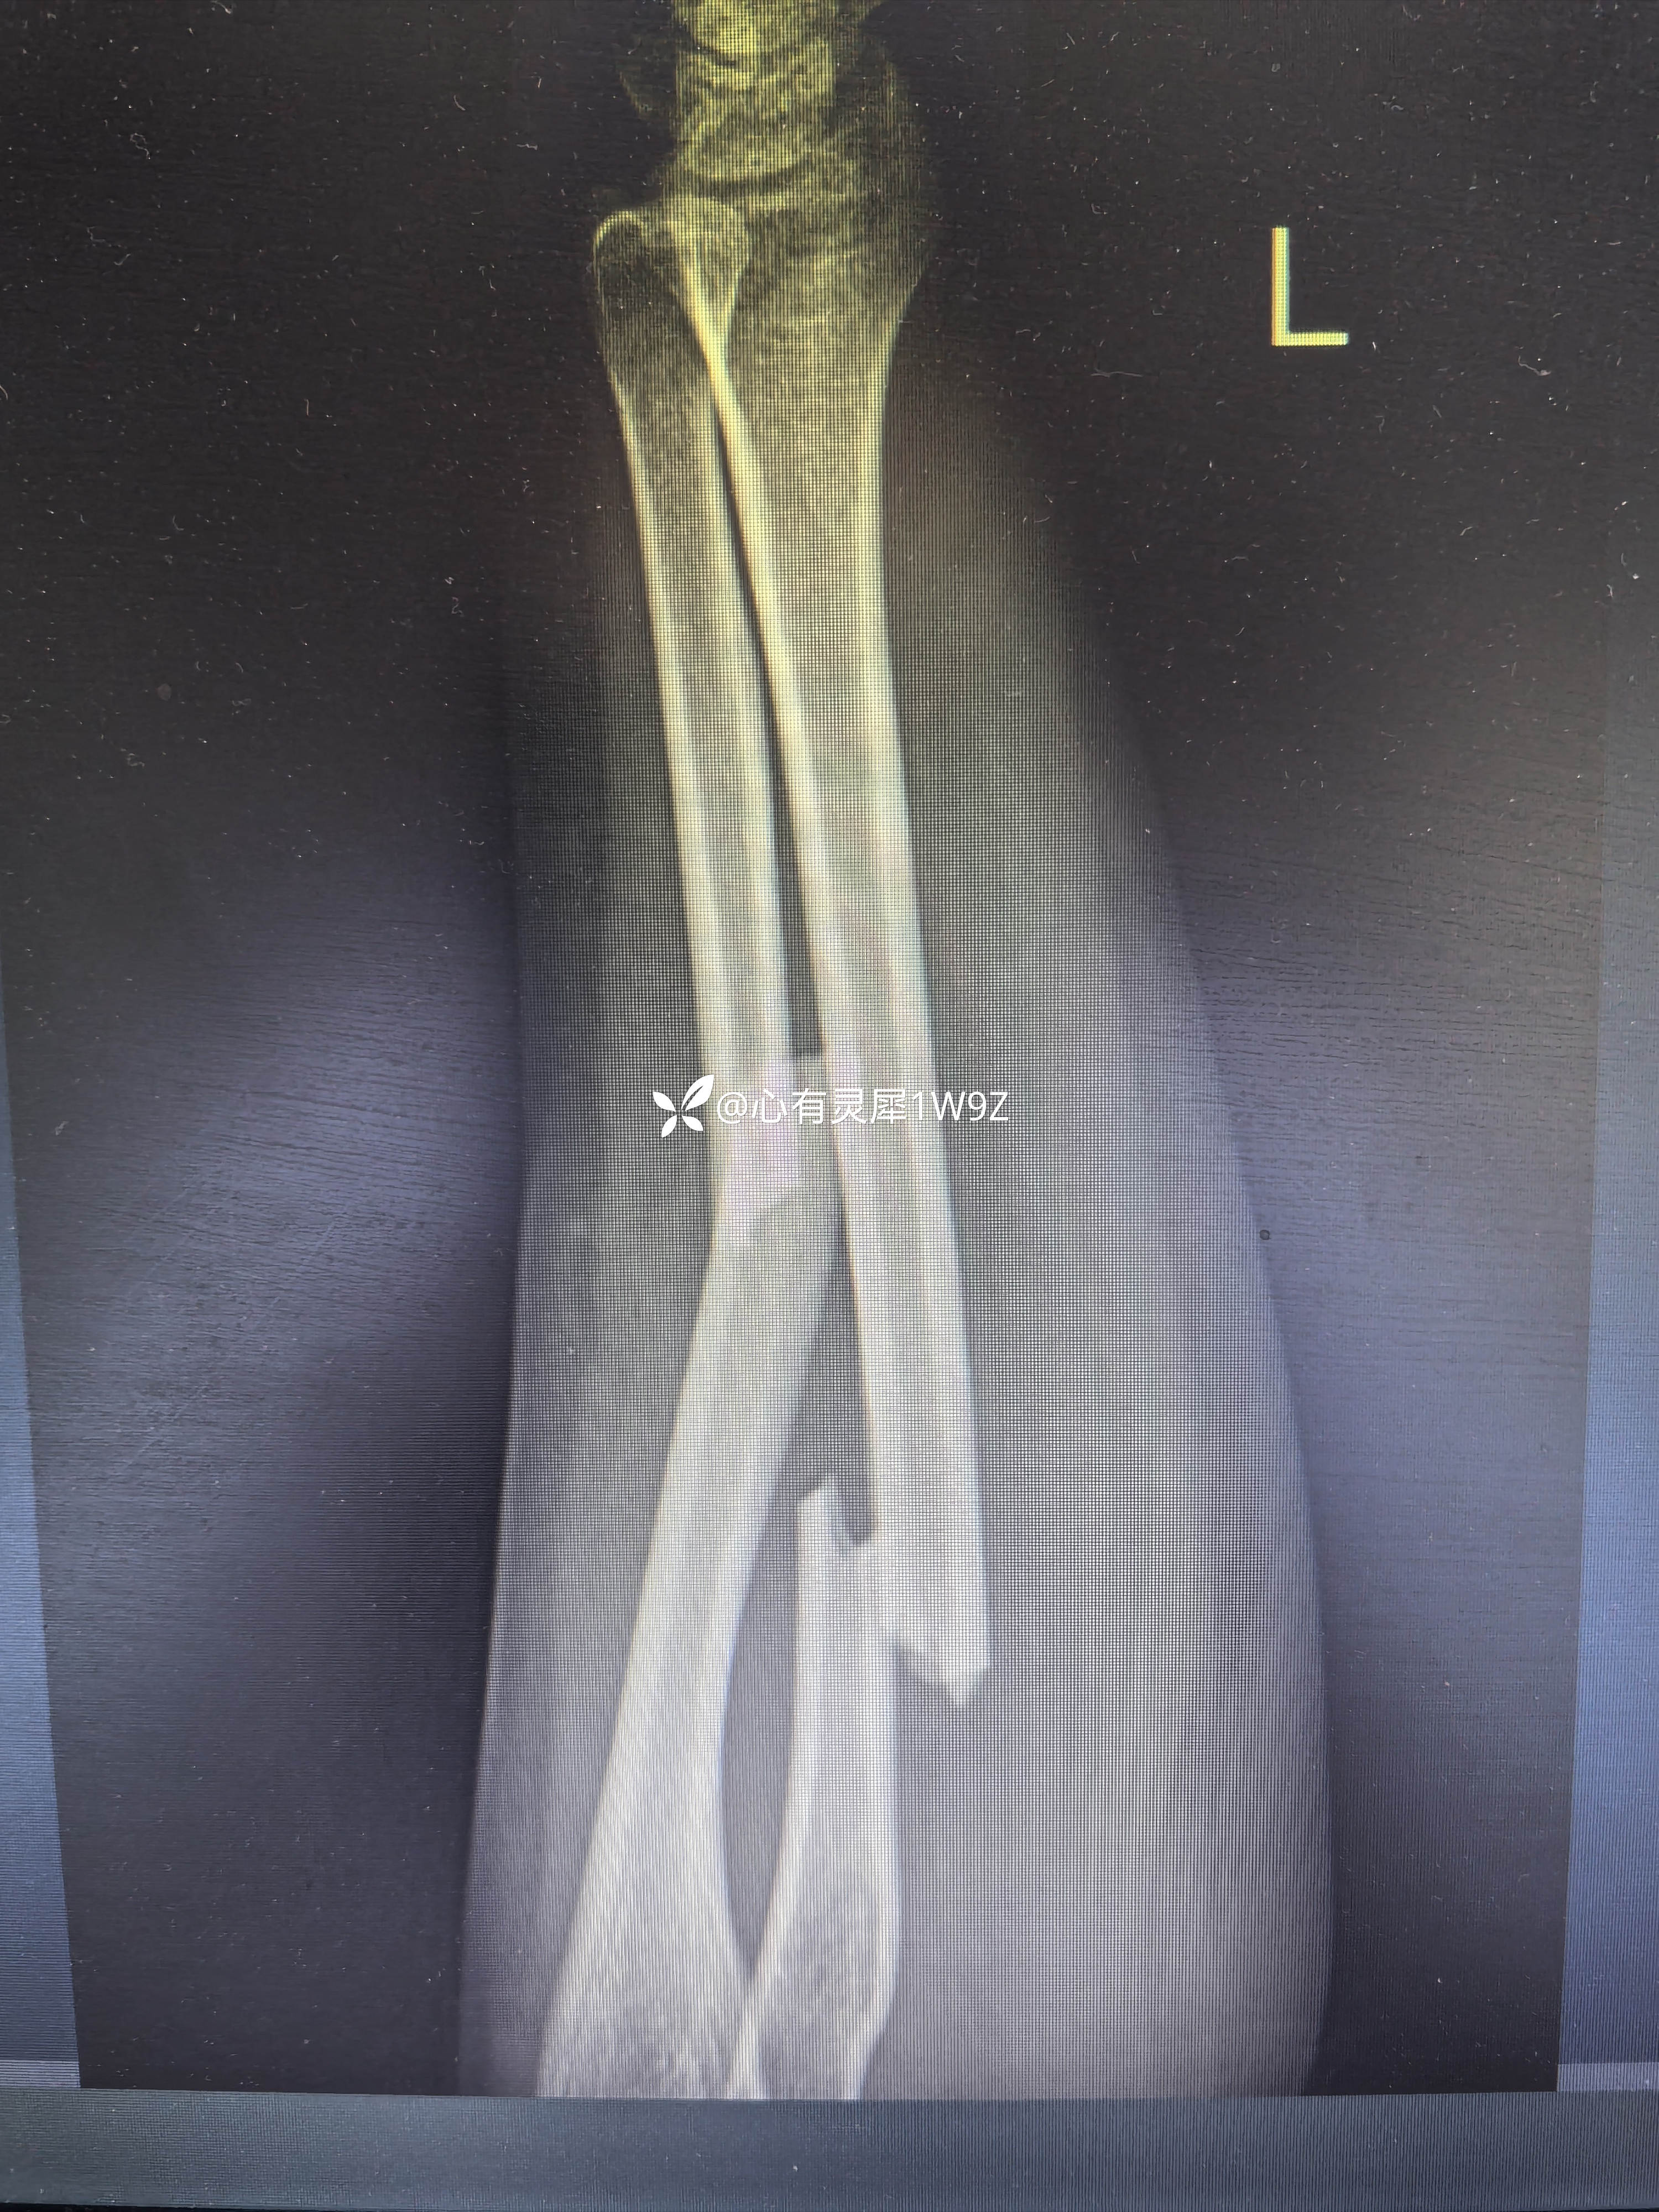

尺桡骨双骨折钢板内固定

【临床诊断】:左侧尺桡骨双骨折